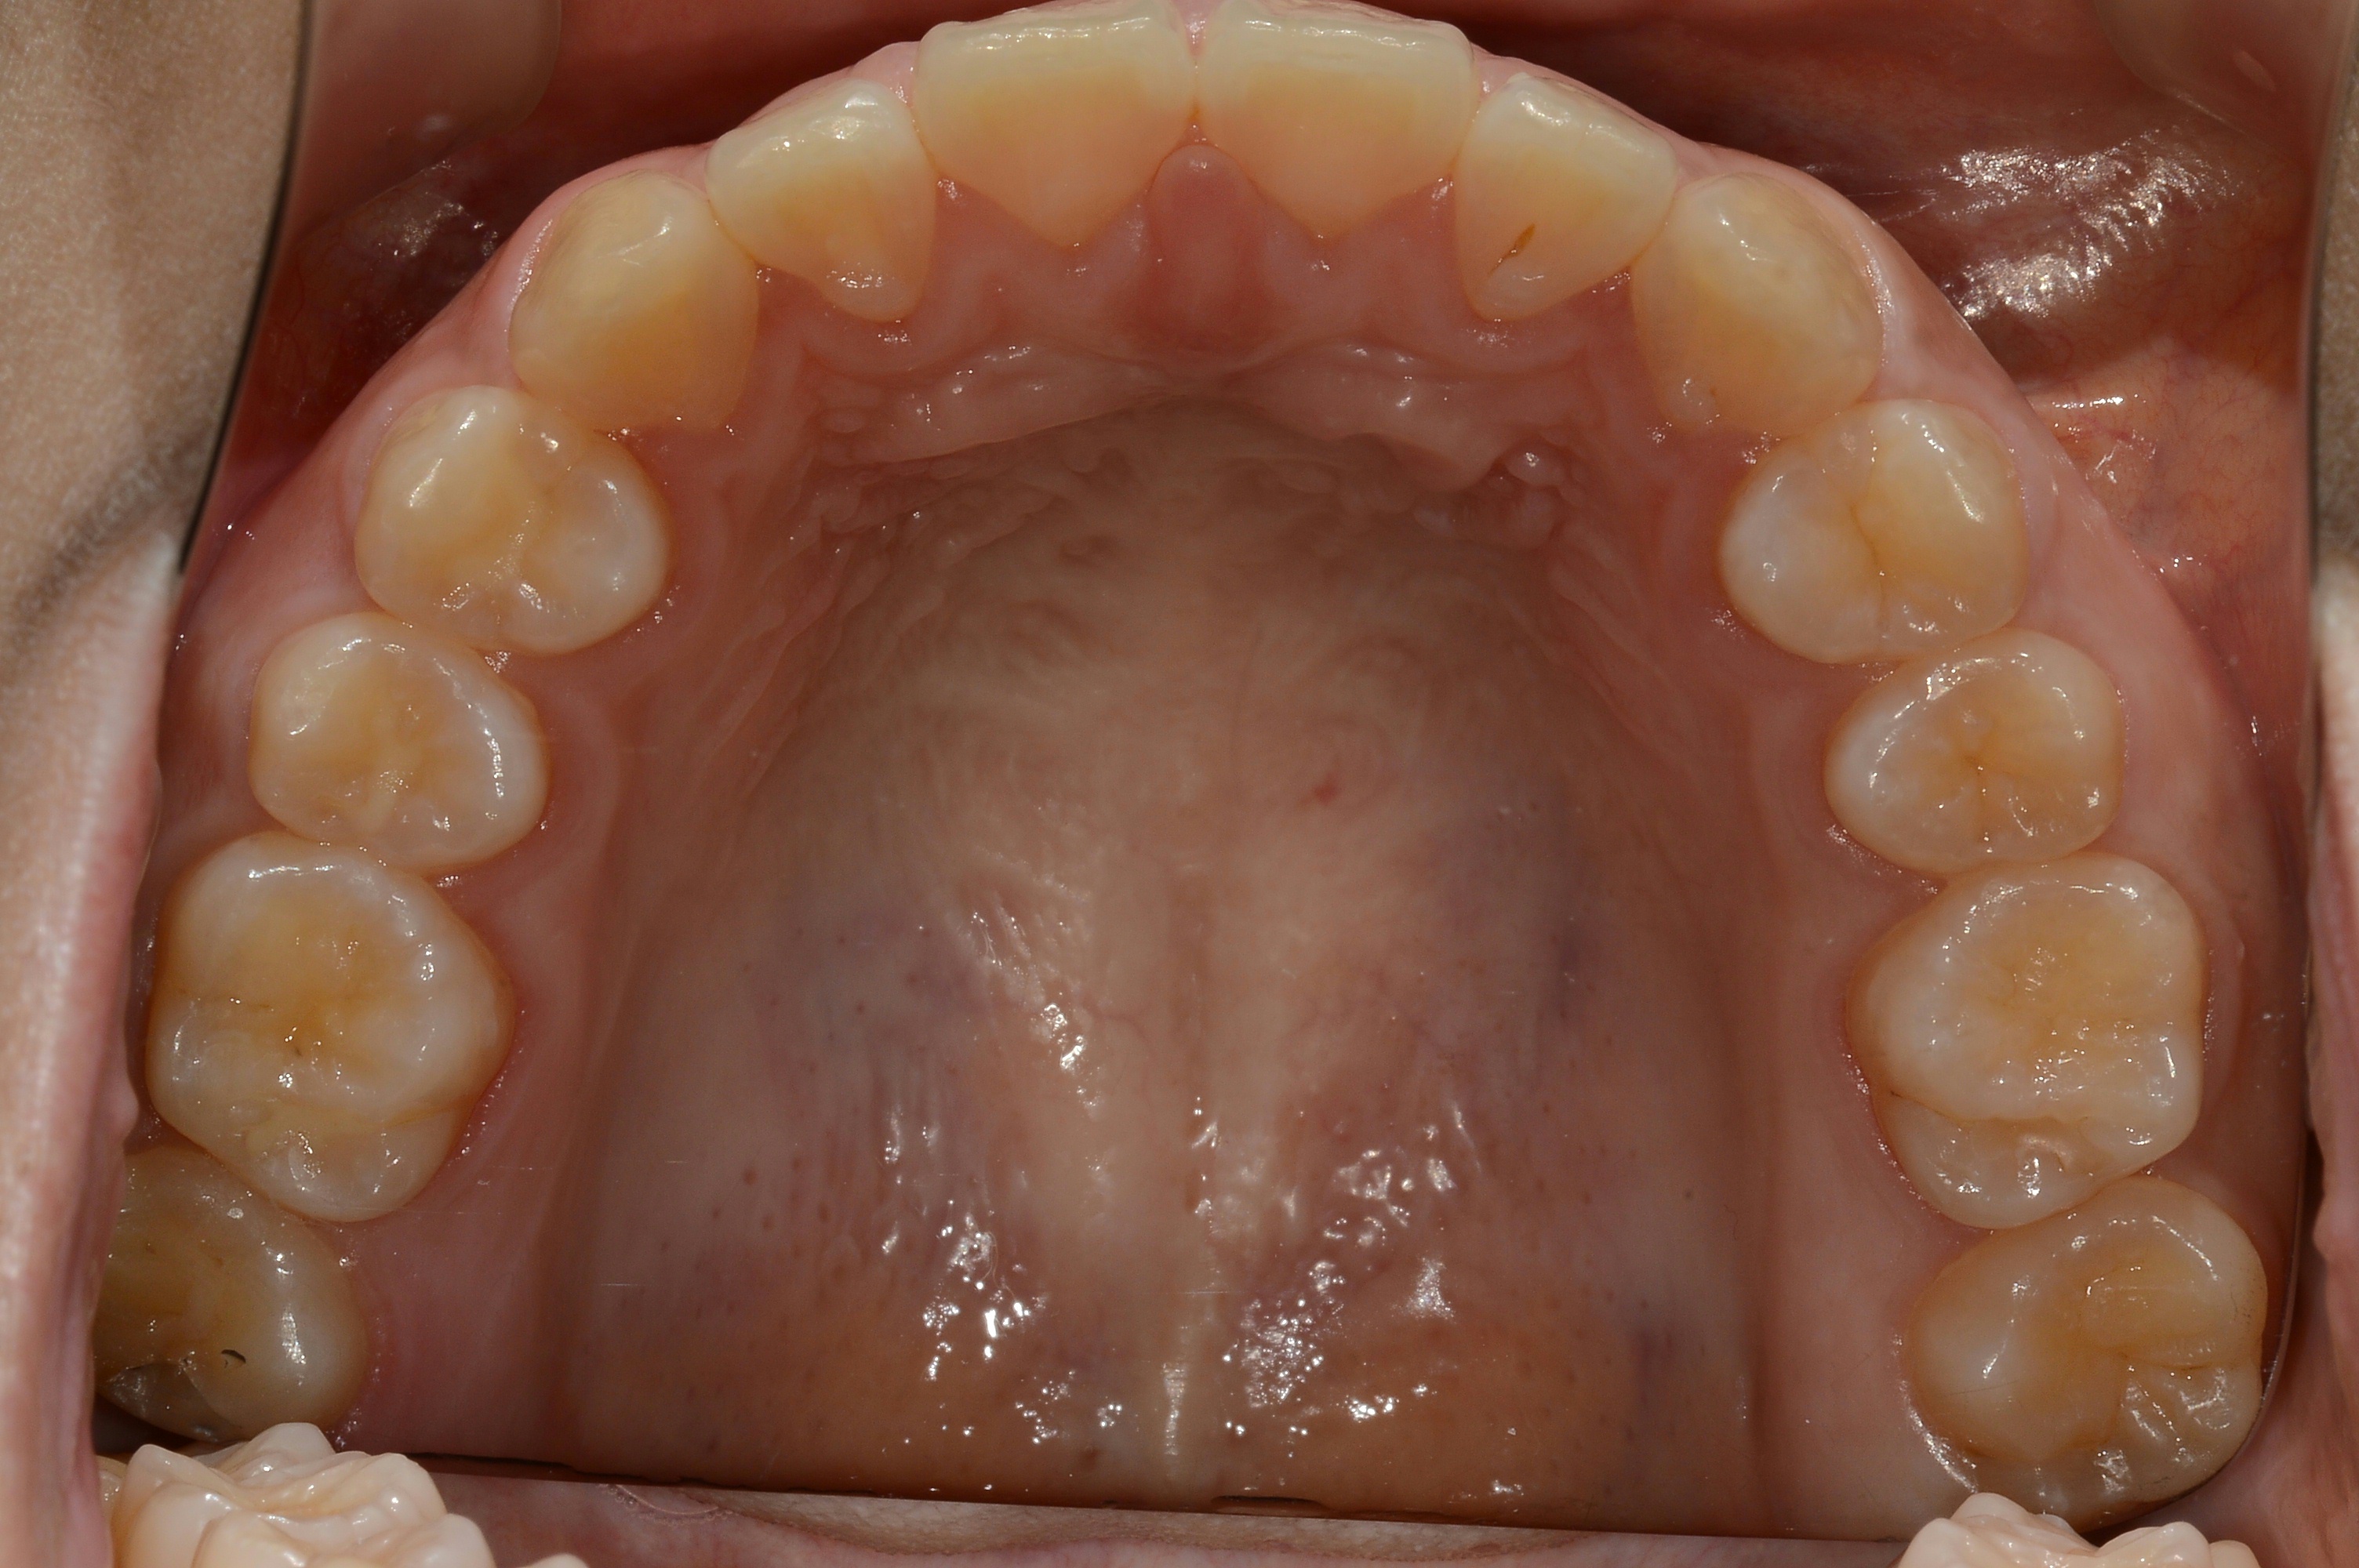

치료 후 사진입니다.